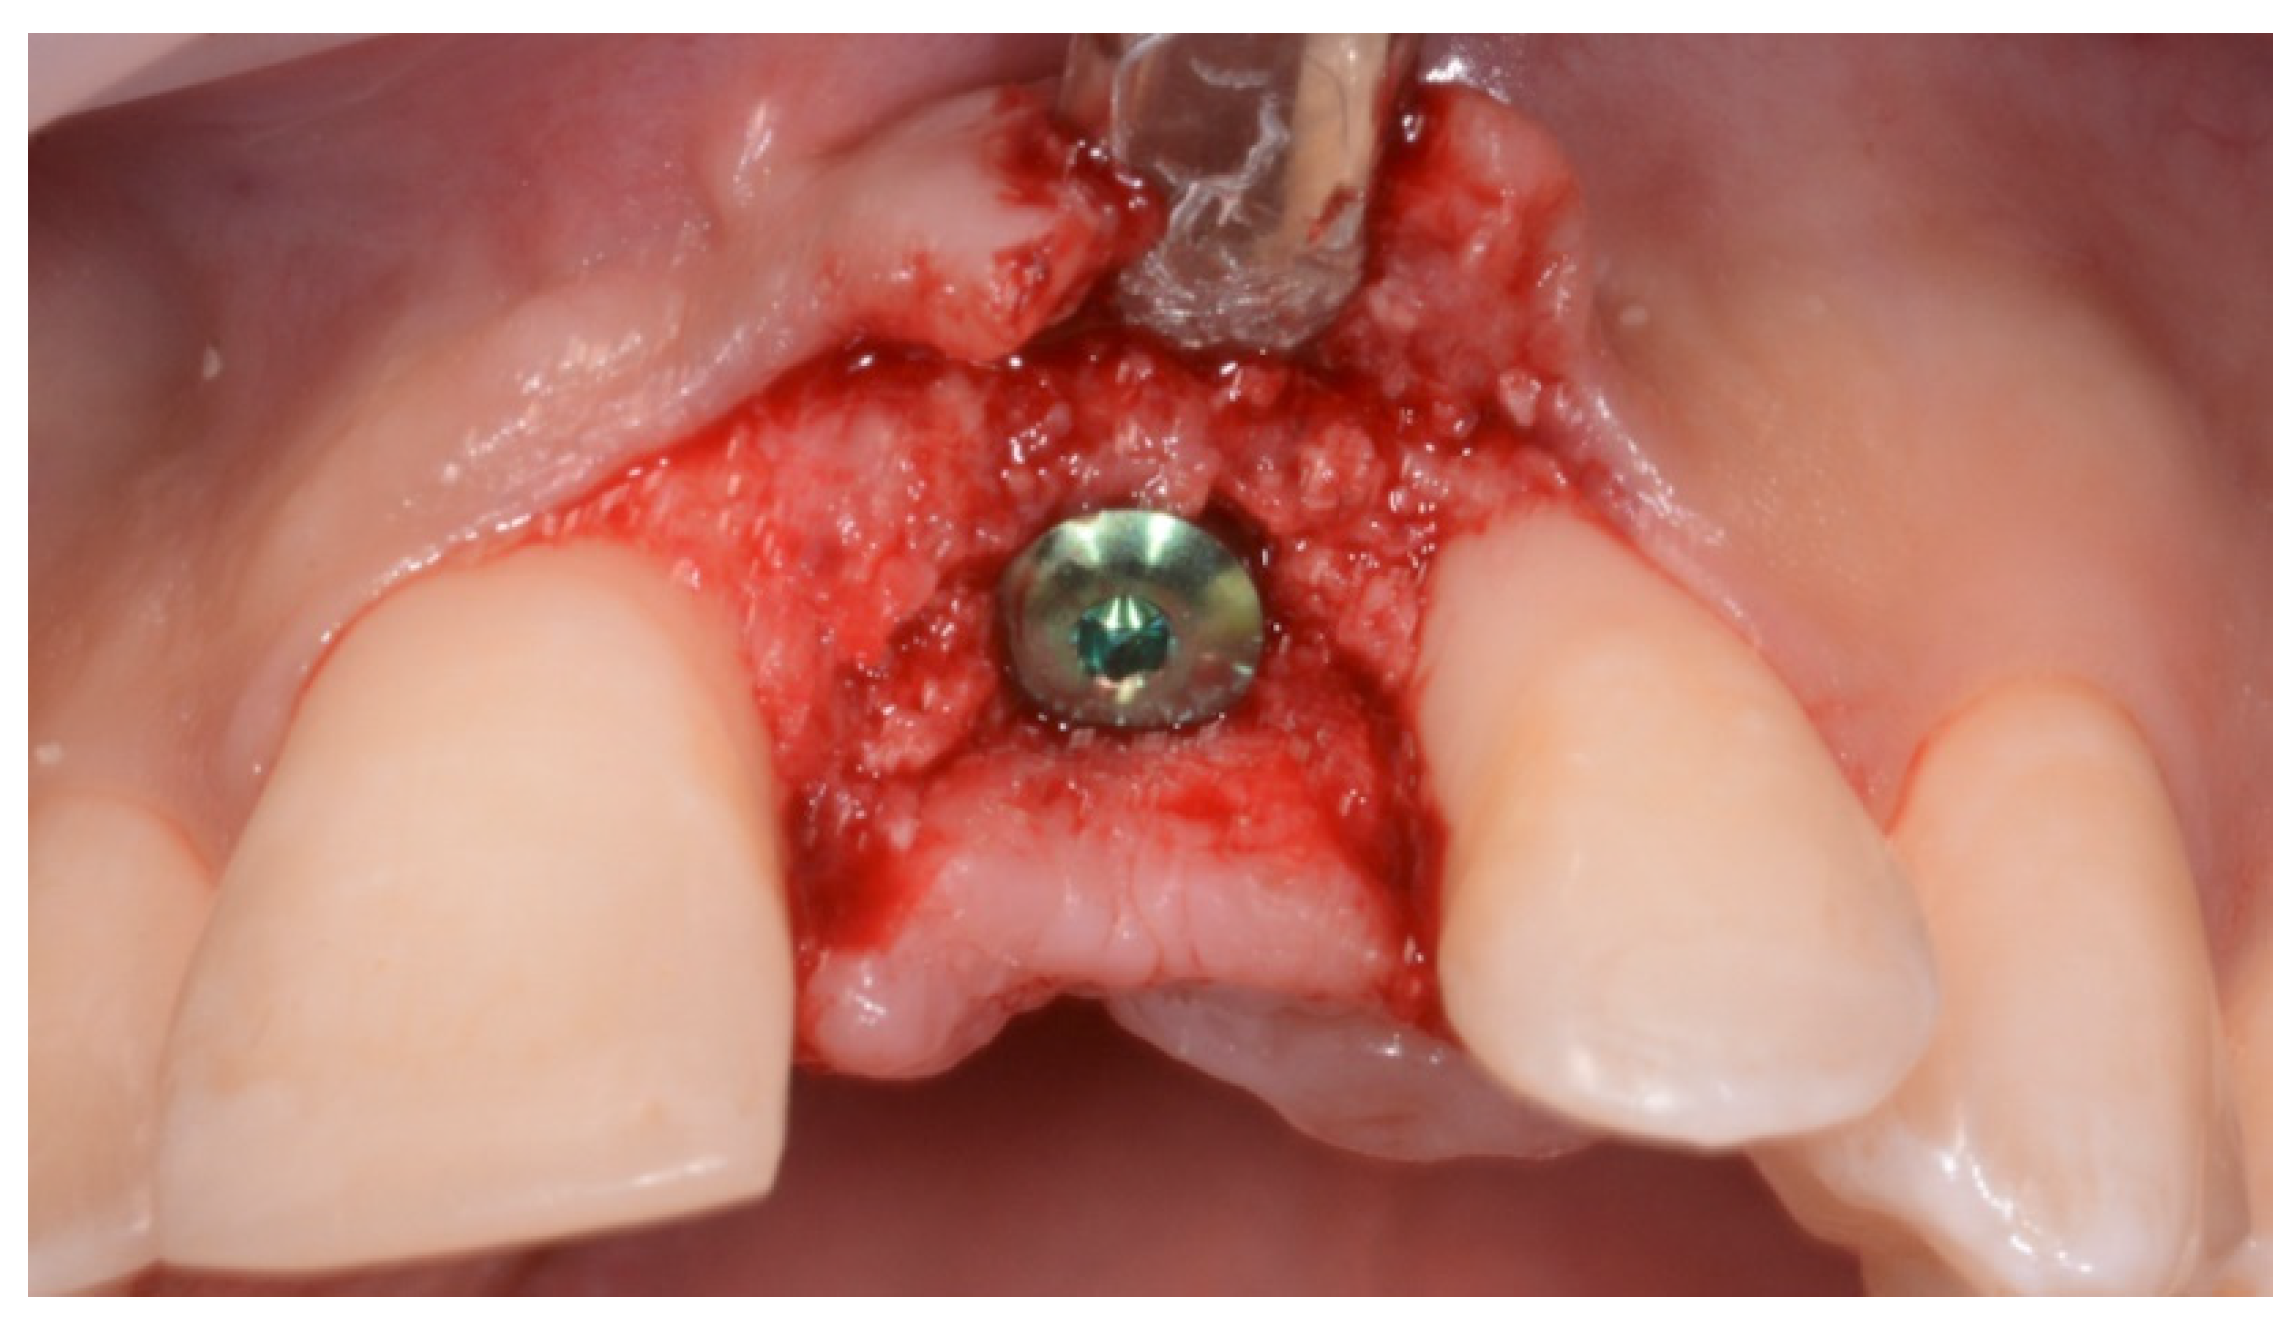

2. Case Presentation